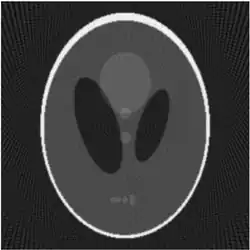

If a function represents an unknown density, then the Radon transform represents the projection data obtained as the output of a tomographic scan. The inverse of the Radon transform can be used to reconstruct the original density from the projection data, and thus it forms the mathematical underpinning for tomographic reconstruction, also known as iterative reconstruction.

The process of reconstruction produces the image (or function in the previous section) from its projection data. Reconstruction is an inverse problem.

Explicit and computationally efficient inversion formulas for the Radon transform and its dual are available. The Radon transform in dimensions can be inverted by the formula:[11] where , and the power of the Laplacian is defined as a pseudo-differential operator if necessary by the Fourier transform: For computational purposes, the power of the Laplacian is commuted with the dual transform to give:[12] where is the Hilbert transform with respect to the s variable. In two dimensions, the operator appears in image processing as a ramp filter.[13] One can prove directly from the Fourier slice theorem and change of variables for integration that for a compactly supported continuous function of two variables: Thus in an image processing context the original image can be recovered from the 'sinogram' data by applying a ramp filter (in the variable) and then back-projecting. As the filtering step can be performed efficiently (for example using digital signal processing techniques) and the back projection step is simply an accumulation of values in the pixels of the image, this results in a highly efficient, and hence widely used, algorithm.